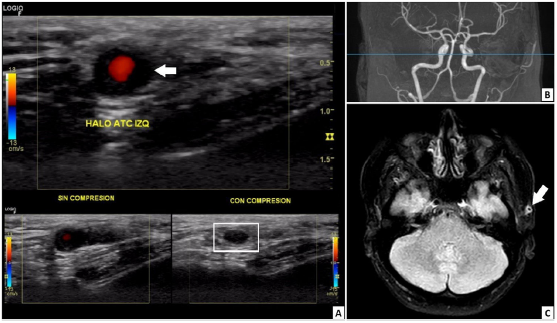

At the beginning of 2021, the patient perceived a subtle thickening in the left temporal artery with no associated symptoms. However, three months before her presentation (August 2021), she manifested left temporal headache radiating toward the left maxillary region, local dysesthesias, photophobia, and ipsilateral mandibular claudication. An outpatient brain computed tomography (CT) was normal, and the Doppler ultrasound of temporal arteries showed positive "halo" and "compression" signs in the left common superficial temporal artery (Fig. 2). With the former result, the patient was admitted to the emergency department. On physical examination, the left temporal artery was thickened compared to the contralateral, pulses were present, no skin lesions on the scalp were evident, and her ocular fundus and visual acuity were normal. Fig. 3 presents the timeline of events, and the Table 1 summarizes relevant laboratory data.

Fig. 2 (A) Doppler ultrasound image with a multifrequency linear transducer. Left common superficial temporal artery with hypoechoic, concentric, and homogeneous wall thickening well delineated toward the luminal side, up to 1.9 mm in the transverse plane, which corresponds to the halo sign (white arrow), and remains visible after extrinsic compression (white box below), configuring the non-compressible sign. No alterations were found in the right common superficial temporal artery, its branches, or axillary arteries. (B) 1.5-Tesla cerebral magnetic resonance angiography images did not detect vascular lesions. (C) Fluid attenuated inversion recovery (FLAIR) sequence in the axial plane. Homogenous wall thickening with homogeneous contrast uptake was observed in the left superficial temporal artery (white arrow), suggesting temporal arteritis.

A cerebral magnetic resonance angiography (MRA) revealed vasculitis in the left superficial temporal artery without any other abnormal findings (Fig. 2). Chest CT, transthoracic echocardiogram, and thoracoabdominal MRA were normal. Additionally, a left superficial temporal artery biopsy evidenced panmural arteritis with marked eosinophilic infiltration (Fig. 4). Furthermore, a peripheral blood flow cytometry revealed a relative increase in eosinophils (7.1%) and 3.1% of T lymphocytes with aberrant immunophenotype (CD2+, CD3-, CD4+, CD5+++, CD45+), without other alterations. Moreover, a new BMA found a hypercellular bone marrow with increased eosinophil precursors (11.4%) without dysplasia. Bone marrow flow cytometry revealed T lymphocytes with the same aberrant immunophenotype detected in peripheral blood. The T-cell receptor rearrangement analysis could not be done because of insufficient material. Subsequently, left temporal arteritis caused by EV associated with L-HES was diagnosed.

Temporal arteritis in patients under the age of 50 years is a rare form of vasculitis with different etiologies to the giant cell arteritis (GCA), the principal cause in patients above 50 years old but absent in younger patients.2 The "halo" and "compression" signs on Doppler ultrasound are usually associated with GCA but could be found in other vasculitis8 (Fig. 2).